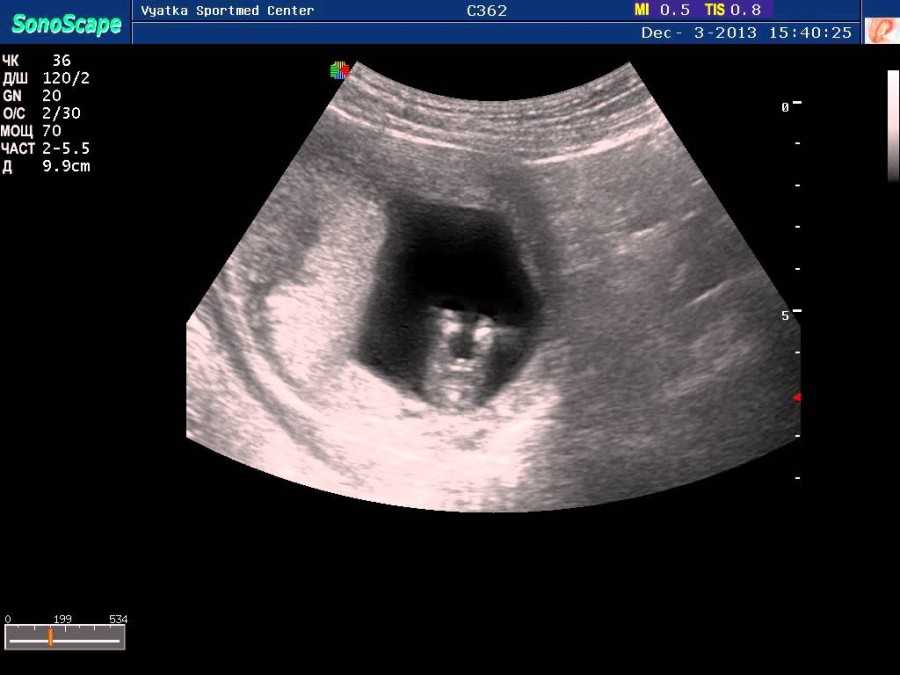

Также показано ультразвуковое исследование плода. Процедура УЗИ позволяет определить срок беременности, толщину плаценты, а также общее состояние яичников и пуповины.

На УЗИ плода на 9 неделе определяется толщина плаценты и общее состояние пуповины. При помощи допплера, будущая мама может отметить частоту сердечных сокращений малыша. Хотя многие внутренние органы уже достаточно развиты, это не всегда можно увидеть на УЗИ на 9 неделе.

Внутренние органы крохи еще могут выступать в виде пупочной грыжи, но нет повода для беспокойства, ведь это совершенно нормальное явление.

На УЗИ на данном сроке обязательным является общая оценка состояния яичников.

УЗИ на сроке 9 недель